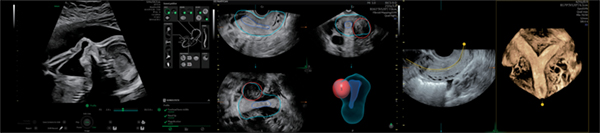

先進のハードウェアとフレキシブルなソフトウェアの融合により誕生したVoluson Unity Architectureが,短時間で迷いない診断をサポートします。

Voluson Signature 18は,AIを用いて開発された多くのクリニカルツールを搭載しました。自動化機能が,検査の一貫性と正確性を確保しつつ,反復動作を減らして日常業務の簡素化を目指します。